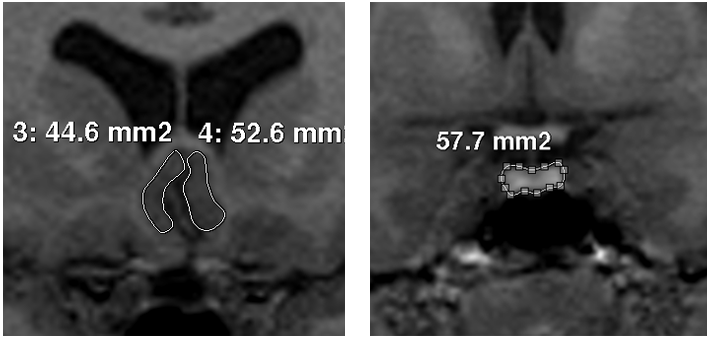

The respective area of interest was traced for PV, PSCV (Figure 1) and ICV, according to methods previously published.11,20 Each pituitary gland was traced around the usually well defined borders of the anterior and posterior lobe, excluding the infundibular stalk. In order to clearly identify the anterior and posterior extends of the structure, pituitary was first identified on a midsaggital slice.28 No empty sellas were noted in the sample. There were no difficulties in the identification of PSCC borders, as the surrounding cerebrospinal fluid and white matter as well as the sulci of the region defined them clearly. We traced from the coronal slice which the internal capsule is first visualized to the natural limit of the gyrus, with the inferior border of the corpus callosum as superior boundary and the medial border of the gyrus rectus as inferior boundary.20

Figure 1 Images of the tracings of posterior subgenual cingulate cortex (left) and pituitary gland (right).